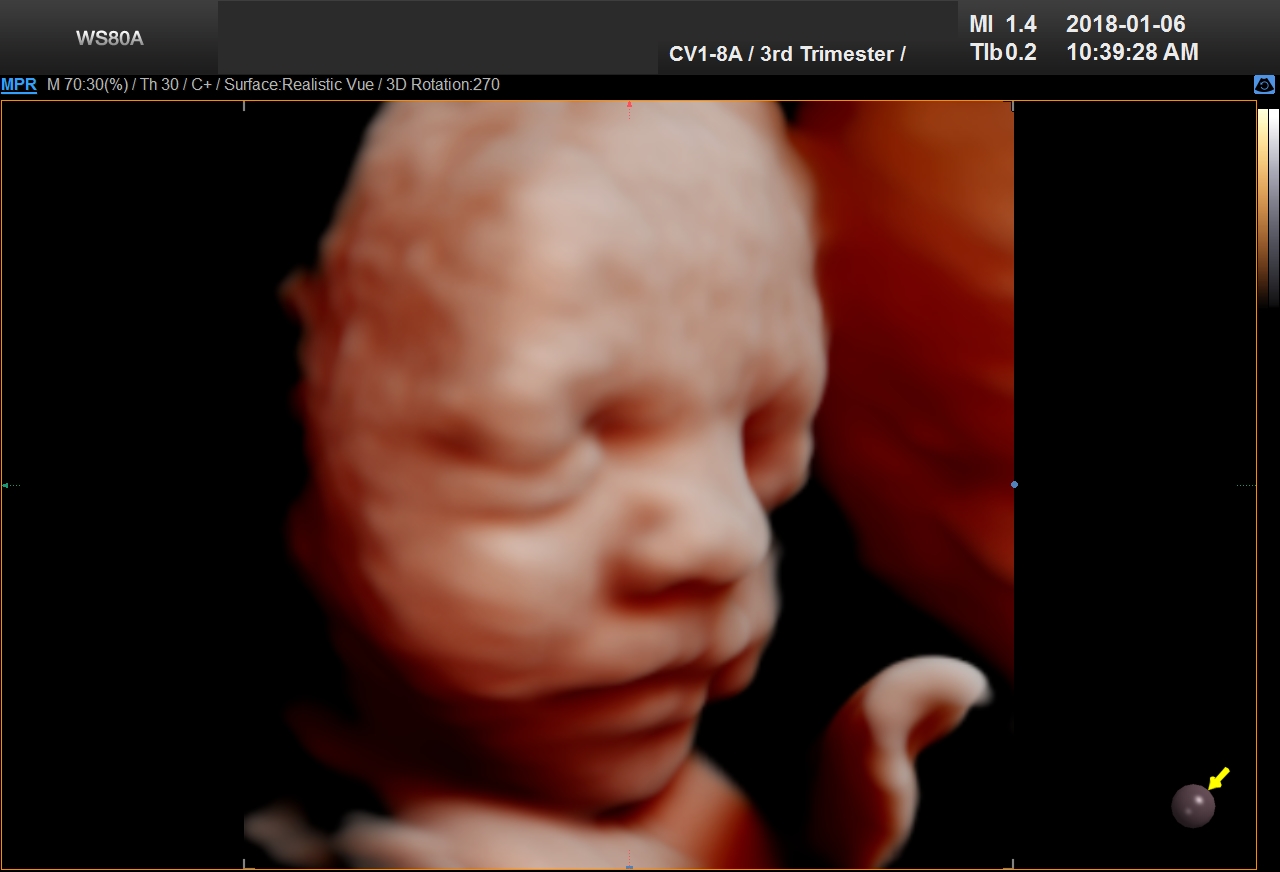

5D Ultrasound is the newest development in pregnancy imaging and it is patented by Samsung. It captures and combines high definition volume data to create automated images with amazing color and clarity. The bond between a new baby and the family gets even stronger when the family can view realistic pictures of baby in a 5D ultrasound.

UC Baby’s Latest 5D Ultrasound Service Offering

UC Baby Calgary is the first facility which brought cutting edge 5D technology to Canada. This cutting edge new ultrasound machine provides realistic pictures of the baby using the most advanced features of ultrasound imaging. We are offering high-definition 5D ultrasound technology to create unforgettable memories without extra cost. This new ultrasound technology allows families to bond stronger to the baby, with clear views of baby’s face and movements. With 5D technology, it is even possible to notice the dimples when baby smiles!

The best time to have a 5D ultrasound is between 24-32 weeks of pregnancy. Our experienced and professionally trained staff are there to amaze the mothers and their families. We also offer free online accounts for captured 2D, 3D, 4D and 5D images / videos in addition to free live broadcast of the whole ultrasound session. This is the fastest and easiest way to share baby’s first pictures and videos with friends and family instantly.